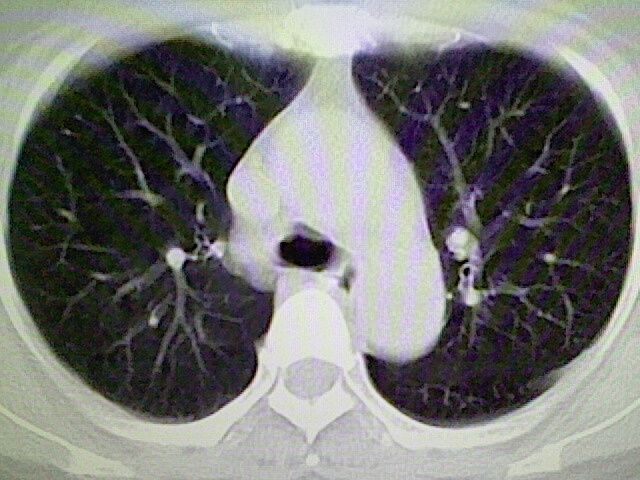

女,52岁,咳嗽,咳痰多日

左下肺陈旧纤维索条!

左肺舌段炎性改变

我见过几例,为炎症后纤维条索

慢性炎症后改变

考虑慢性炎性病灶粘连牵拉改变。

左肺舌叶纤维锁条病变。

左肺上叶下舌段炎症并局部胸膜反应。

左肺舌叶纤维索条影。

左肺舌叶段陈旧性病变

左肺舌段炎性反应。片子的质量太不好了。

左肺舌段炎性

炎性改变

左肺舌叶纤维索条影